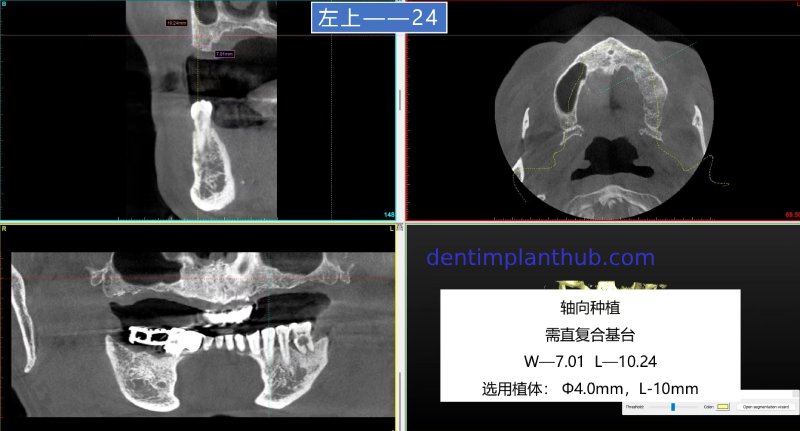

For tooth 24, with a width of 7.01 and a height of 10.24, an implant with a diameter of 4 and a length of 10 is selected. It will be implanted axially, and a straight composite abutment is required.